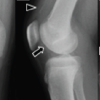

After experiencing persistent knee pain, swelling, and reliance on a crutch for mobility, he was referred back to the orthopedic outpatient clinic. Eight months after the removal of implants, examination demonstrated minimal tenderness but substantial joint effusion and an inability to sustain SLR. This raised the possibility of a partial quadriceps muscle rupture. Inflammatory markers were normal (white cell count 5.3 × 109/L, CRP 6 mg/L). An MRI performed at that time excluded a quadriceps rupture, noting joint effusion, synovitis, and degenerative changes in the tibial plateaus and femoral condyles. Unfortunately, the absence of pain, normal inflammatory markers, and lack of systemic features of infection were falsely reassuring, and MRI changes were attributed to post-traumatic degenerative changes. He was referred for quadriceps strengthening physiotherapy with an emphasis on gradual progression. The patient returned with knee pain, joint effusion, and ongoing limited knee extension 3 months later. Repeat blood work again showed no acute inflammatory changes (ESR 18 mm/h, white cell count 5.6 × 109/L, CRP 7 mg/L). A subsequent MRI (Fig. 2) revealed extensive tricompartmental knee arthritis with joint space narrowing, chondral loss, subarticular geodes, and significant subchondral bone marrow edema, along with a collection in the gastrocnemius.

Figure 2: Magnetic resonance imaging scan of the left knee (a) Sagittal view of the medial tibial joint space. (b) Coronal view of the centre of the knee joint. (c) Sagittal view of the lateral tibial plateau

These findings, along with accompanying effusion and synovitis, raised the possibility of infective arthropathy.